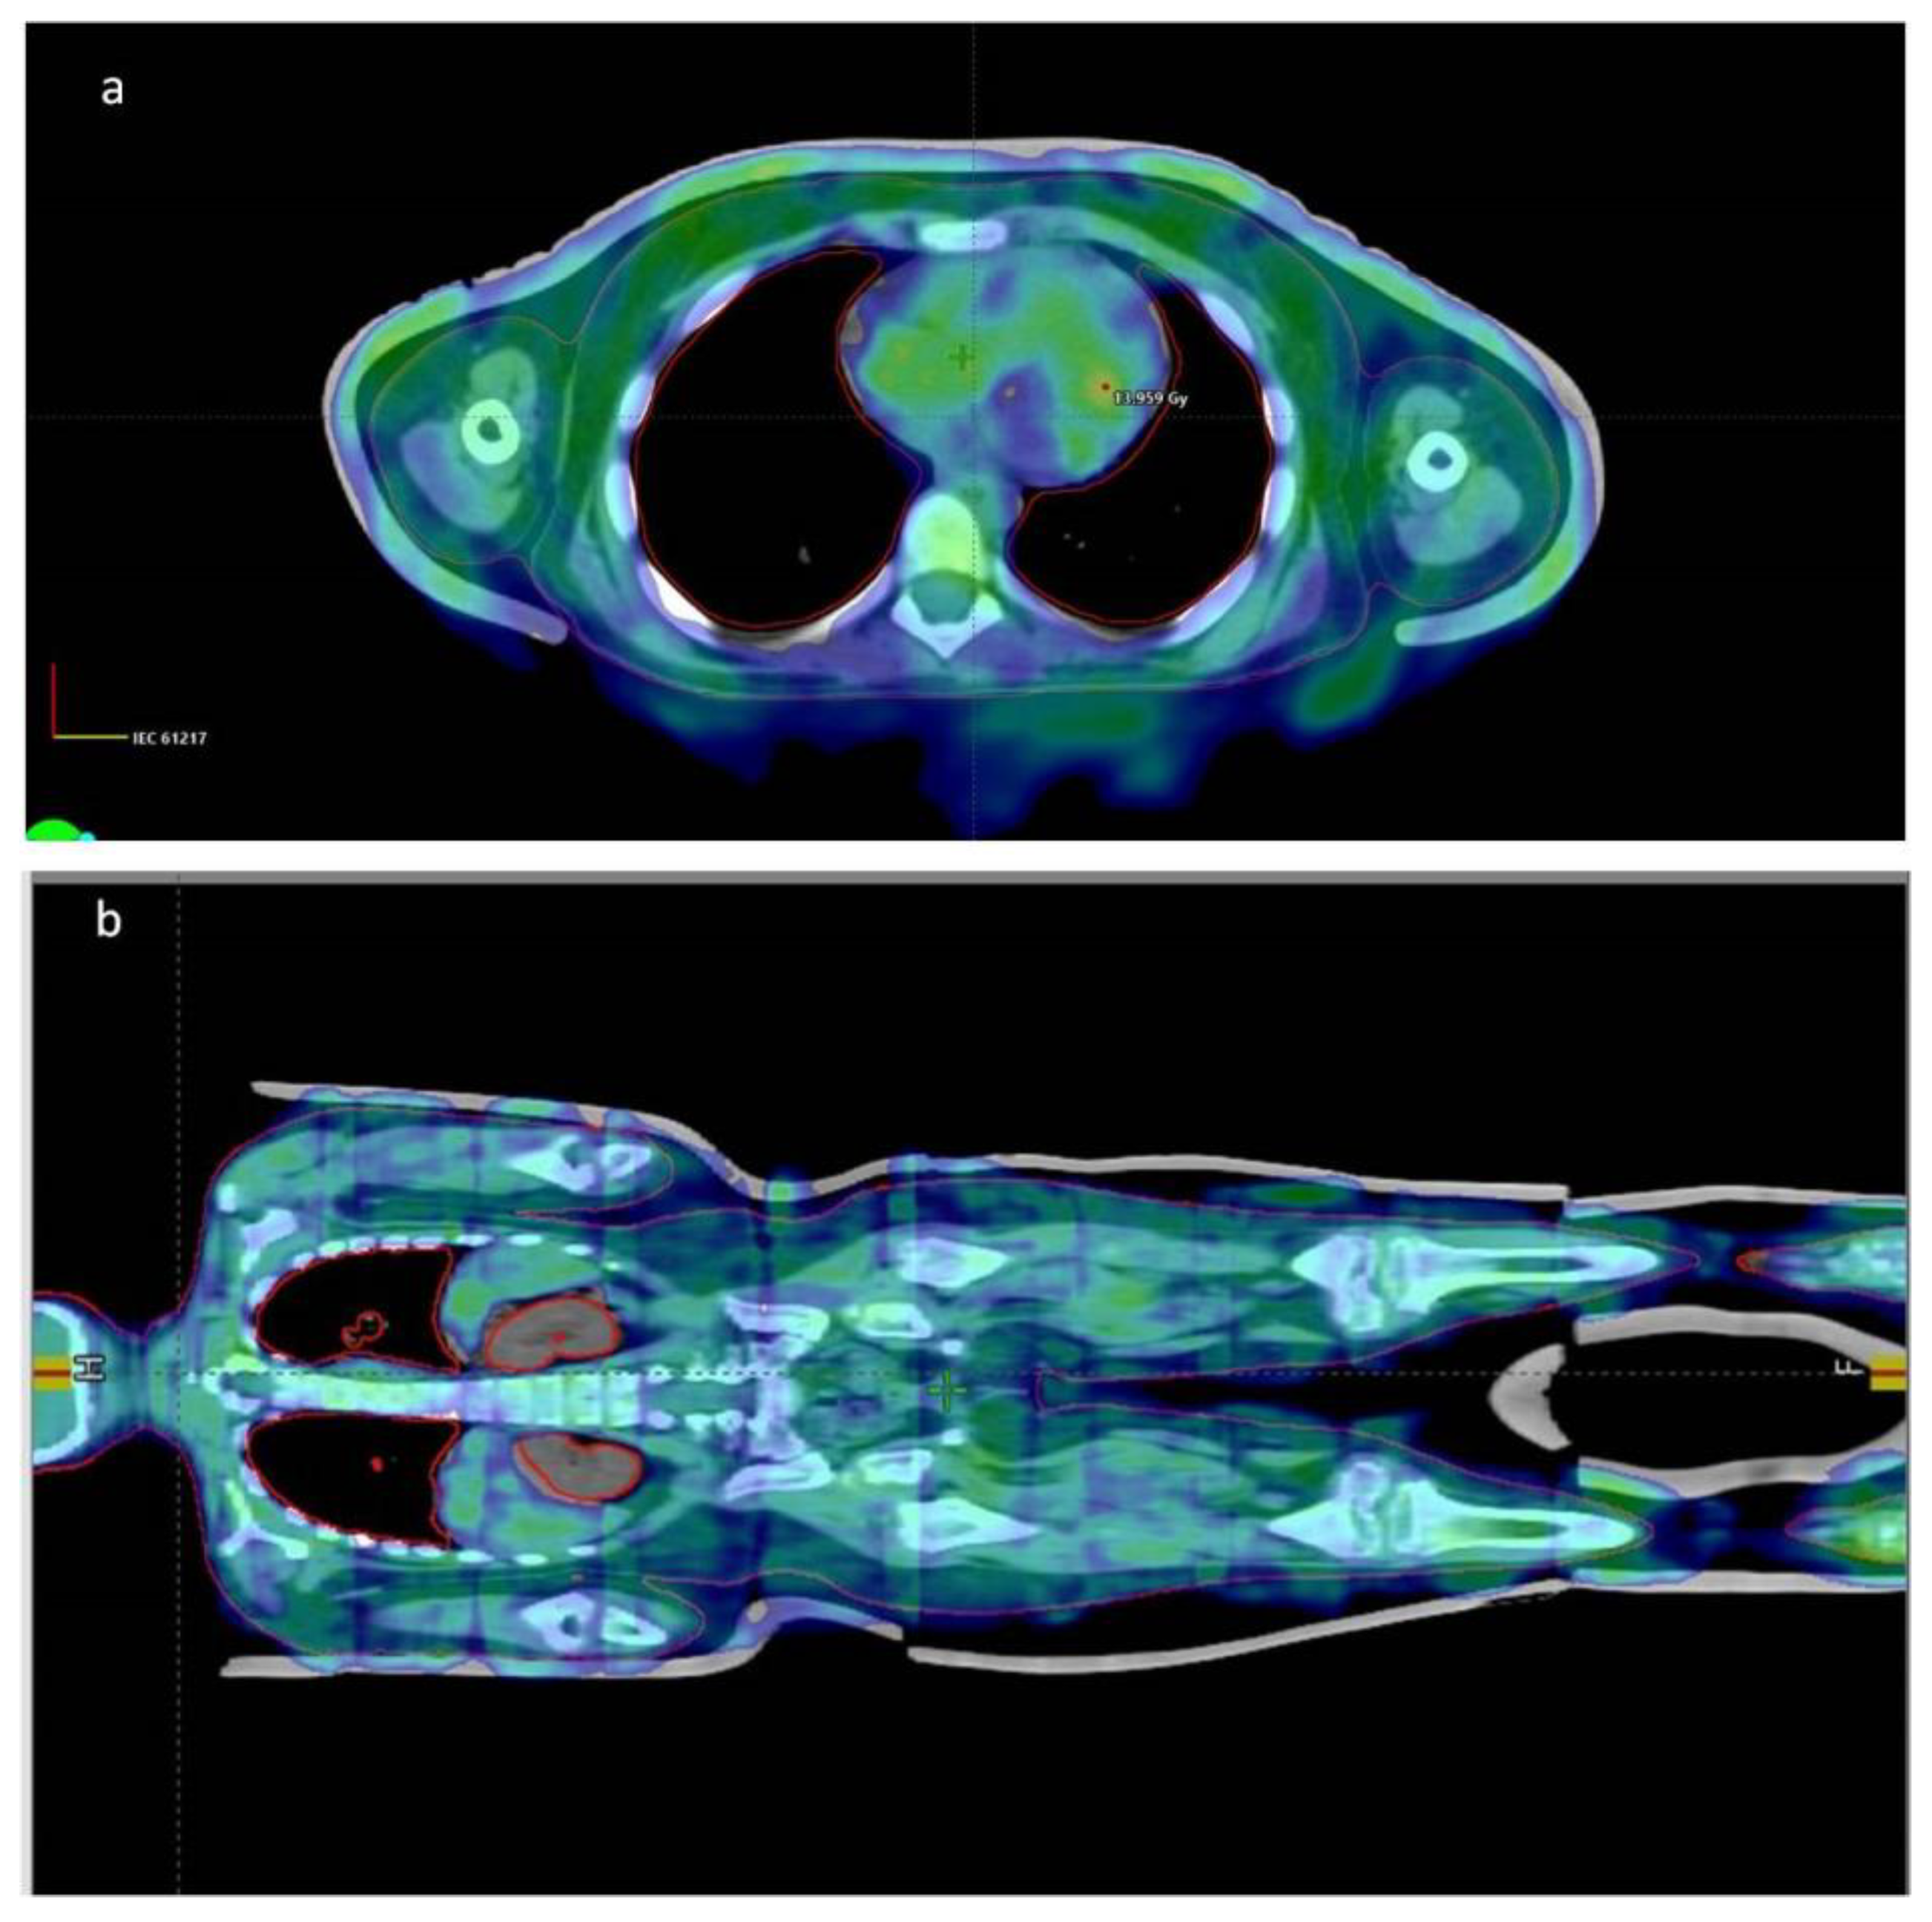

Full Body Surface Coverage with Water-Equivalent Bolus as Novel Technique for Total Body Irradiation before Hematopoietic Stem Cell Transplantation in Pediatric Acute Lymphoid Leukemia

| Technic | VMAT | VMAT | VMAT | VMAT | VMAT/IMRT |

| Arcs/Fields | 18 | 24 | 18 | 20 | 14 Field IMRT + 19 |

| Energy | 6x photon | 6x photon | 6x photon | 6x photon | 6x photon |